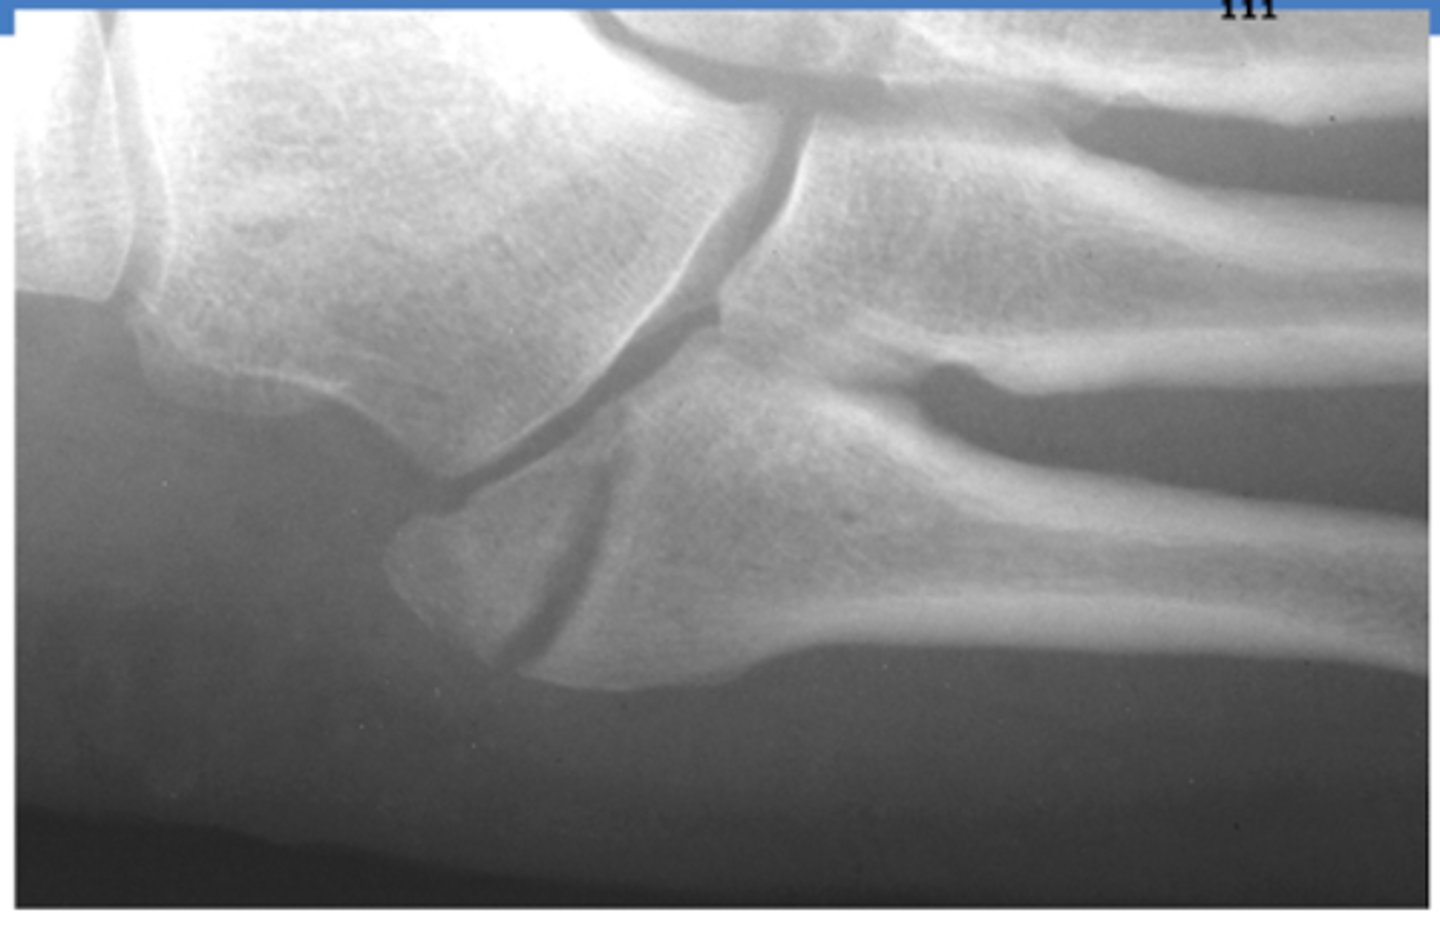

What joint is involved in a Lisfranc injury/fracture?

TMT (tarsometatarsal) joint

- between the articulation of the medial cuneiform and the base of the 2nd MT

What is the treatment for a Lisfranc injury/fracture that is <2mm?

casting for 6 weeks

- cannot bear weight

What is Chopart's Fracture-Dislocation?

Dislocation of the mid-tarsal joints (talonavicular + calcaneocuboid)

Fracture of the calcaneus, cuboid and navicular

What is the treatment for Chopart's Fracture-Dislocation?

open reduction w/ internal fixation